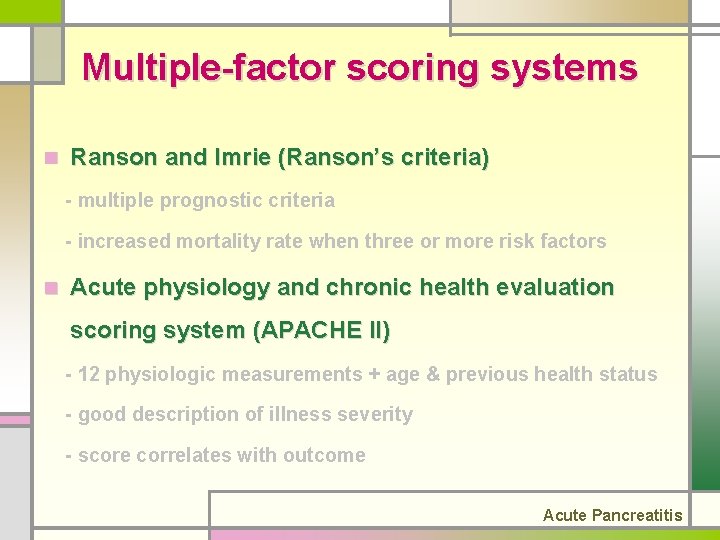

Multiple-factor scoring systems n Ranson and Imrie (Ranson’s criteria) - multiple prognostic criteria - increased mortality rate when three or more risk factors n Acute physiology and chronic health evaluation scoring system (APACHE II) - 12 physiologic measurements + age & previous health status - good description of illness severity - score correlates with outcome Acute Pancreatitis